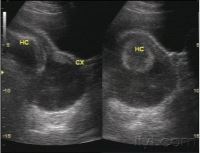

根据您宫颈机能不全的症状,给您推荐的: 妇产科

• 妇产科